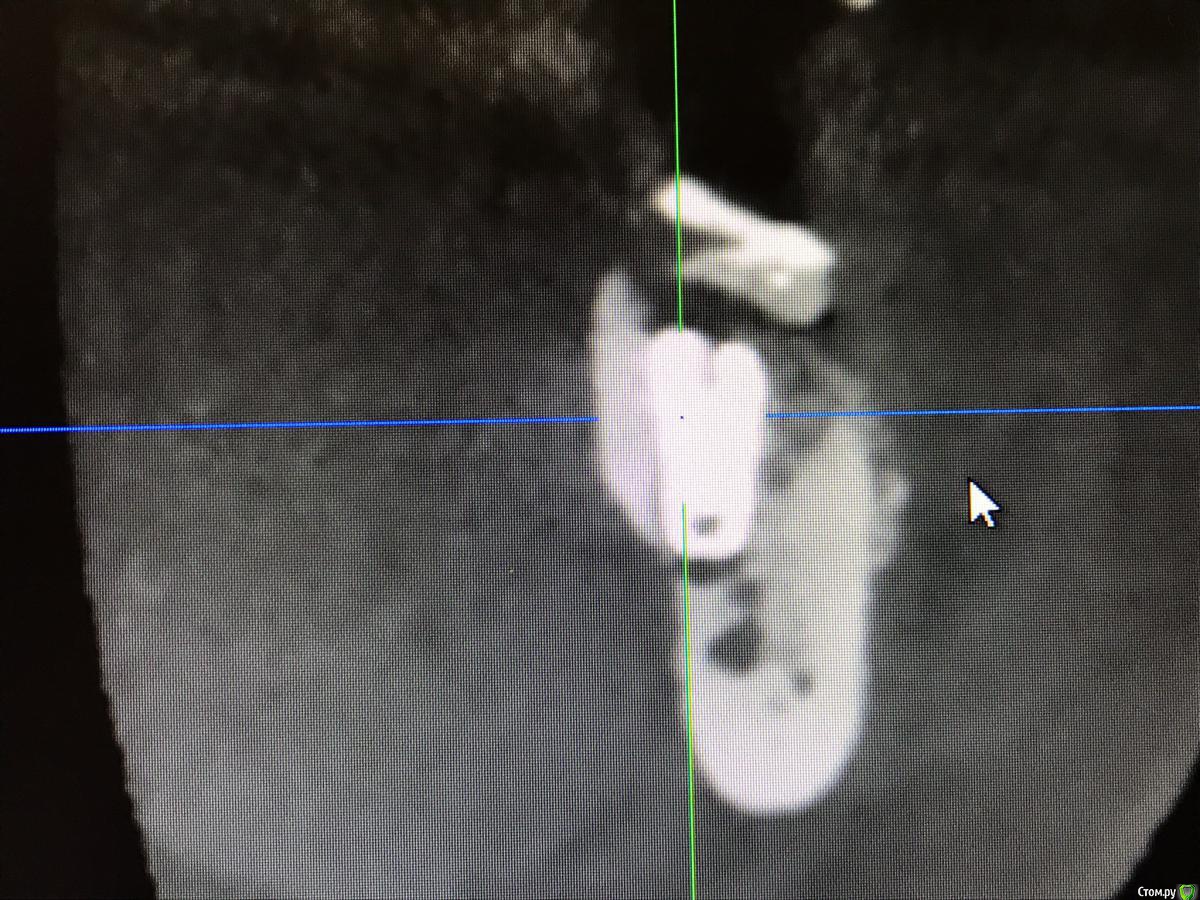

колесников Опубликовано 22 апреля, 2019 Поделиться Опубликовано 22 апреля, 2019 (изменено) И снова профайл спасает жизнь (облегчает жизнь имплантолога)Стандартная ситуация:36 периодонтит в стадии обострения с грануляциями,эксудацией,резорбцией компактной пластинки,дефицитом прикреплённой слизистой вестибулярного. Одна хирургия. Ноябрь 2018. Удаление,кюретаж,имплант Astra tech profile 4.5x9 под заглушку,торк около нуля. Вестибулярного сст,консервация графтом Sureoss 0,5 чипс с APRF,закрытие шайбой по Ноймайеру. Через неделю шайба несостоятельна-удалена. Пациентка созрела на удаление 37го. Выполнена декоронация в связи с отъездом пациентки,далее через 2 недели удаление и имплантация 37го. Промежуточный осмотр в январе. В марте установлены формирователи . Апрель контрольный осмотр. Периотест -5. Направлена на протезирование. Изменено 22 апреля, 2019 пользователем колесников 4 Ссылка на комментарий